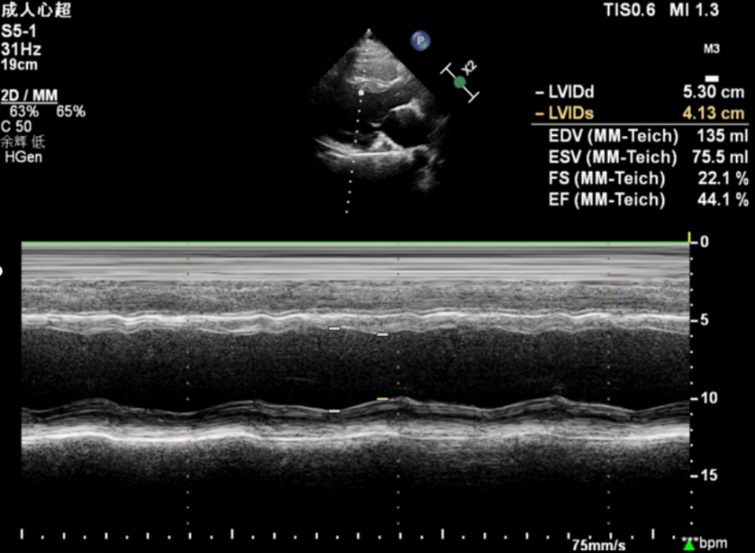

17岁的小敖胸闷、憋气已有2年,近5个月来症状加重,在当地医院进行心脏超声检查发现左心室射血分数(LVEF)降低,为寻求进一步治疗来到青大附院市南院区心血管内科门诊。辛辉主任、高娟主治医师进行详细检查后发现,患者LVEF为44%,且伴有左心扩大、左心室壁炎性表现、左心室收缩运动异常、左心室心肌过度小梁化等,初步诊断为慢性心力衰竭急性发作、炎性心肌病。在进一步询问病史后,治疗团队了解到患者舅舅患有全身肌肉萎缩、瘫痪,两名表弟患有轻度肌肉萎缩,这引起了团队的警觉,立即组织放射科、神经内科、风湿免疫科、心脏超声科、肾病科等多学科专家进行疑难病例讨论。